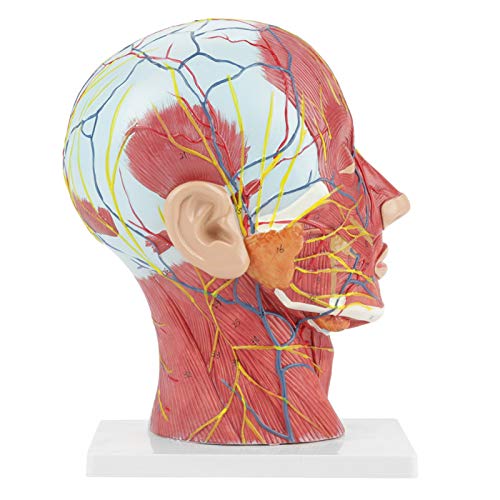

Zeer gedetailleerde getallen gemarkeerd, verdiepen het begrip van de structuur van het menselijk brein, vasculaire structuren

De ene kant toont interne structuur, de andere toont spier- en vasculaire structuur

De ene kant is voorzien van interne anatomie, de andere toont spier- en vasculaire anatomie. Zeer gedetailleerde getallen gemarkeerd, verdiepen het begrip van de structuur van de menselijke hersenen, vasculaire structuren. De gehele structuur is stevig gemonteerd op een kunststof basis, gemakkelijk te observeren. Het model is gemaakt van PVC-kunststof, dat corrosiebestendig, licht is en een hoge sterkte heeft. Toepasbaar op scholen, ziekenhuis, lichamelijke gezondheidsonderwijs, kan als leerhulpmiddel worden gebruikt.

Rode lijn: Artery

Blauwe lijn: Ader

Gele lijn: Zenuw